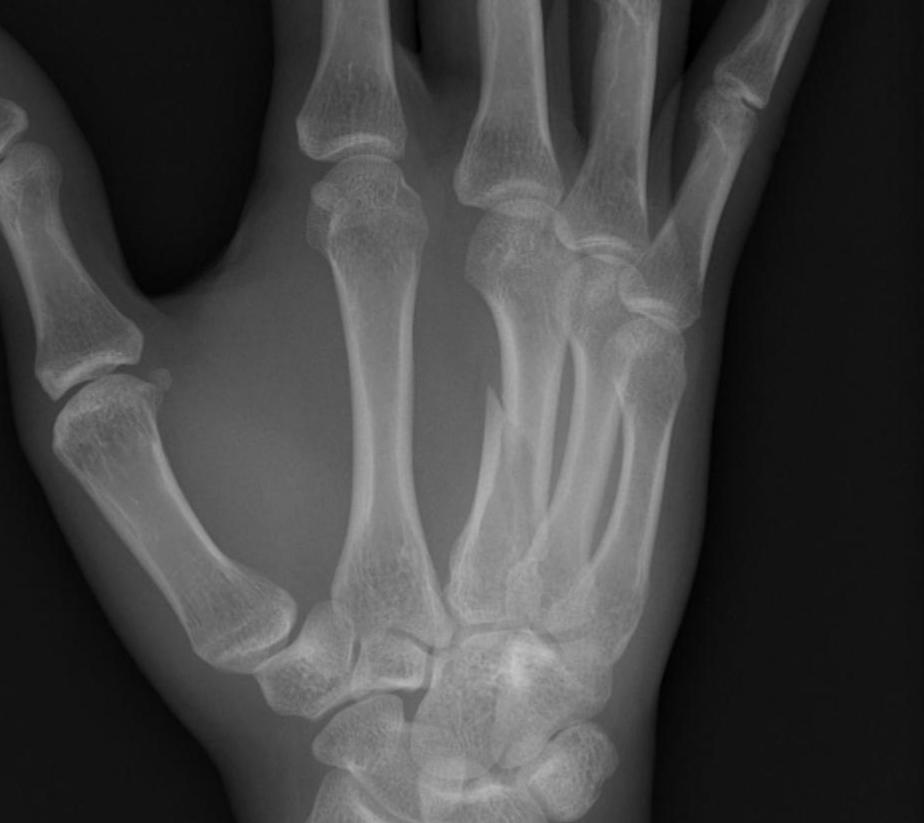

2. Metacarpal Shaft Fracture

Acceptable Deformity

Rotation < 5o

10o / 20o / 30o / 40o in IF / MF / RF / LF

< 5 mm shortening